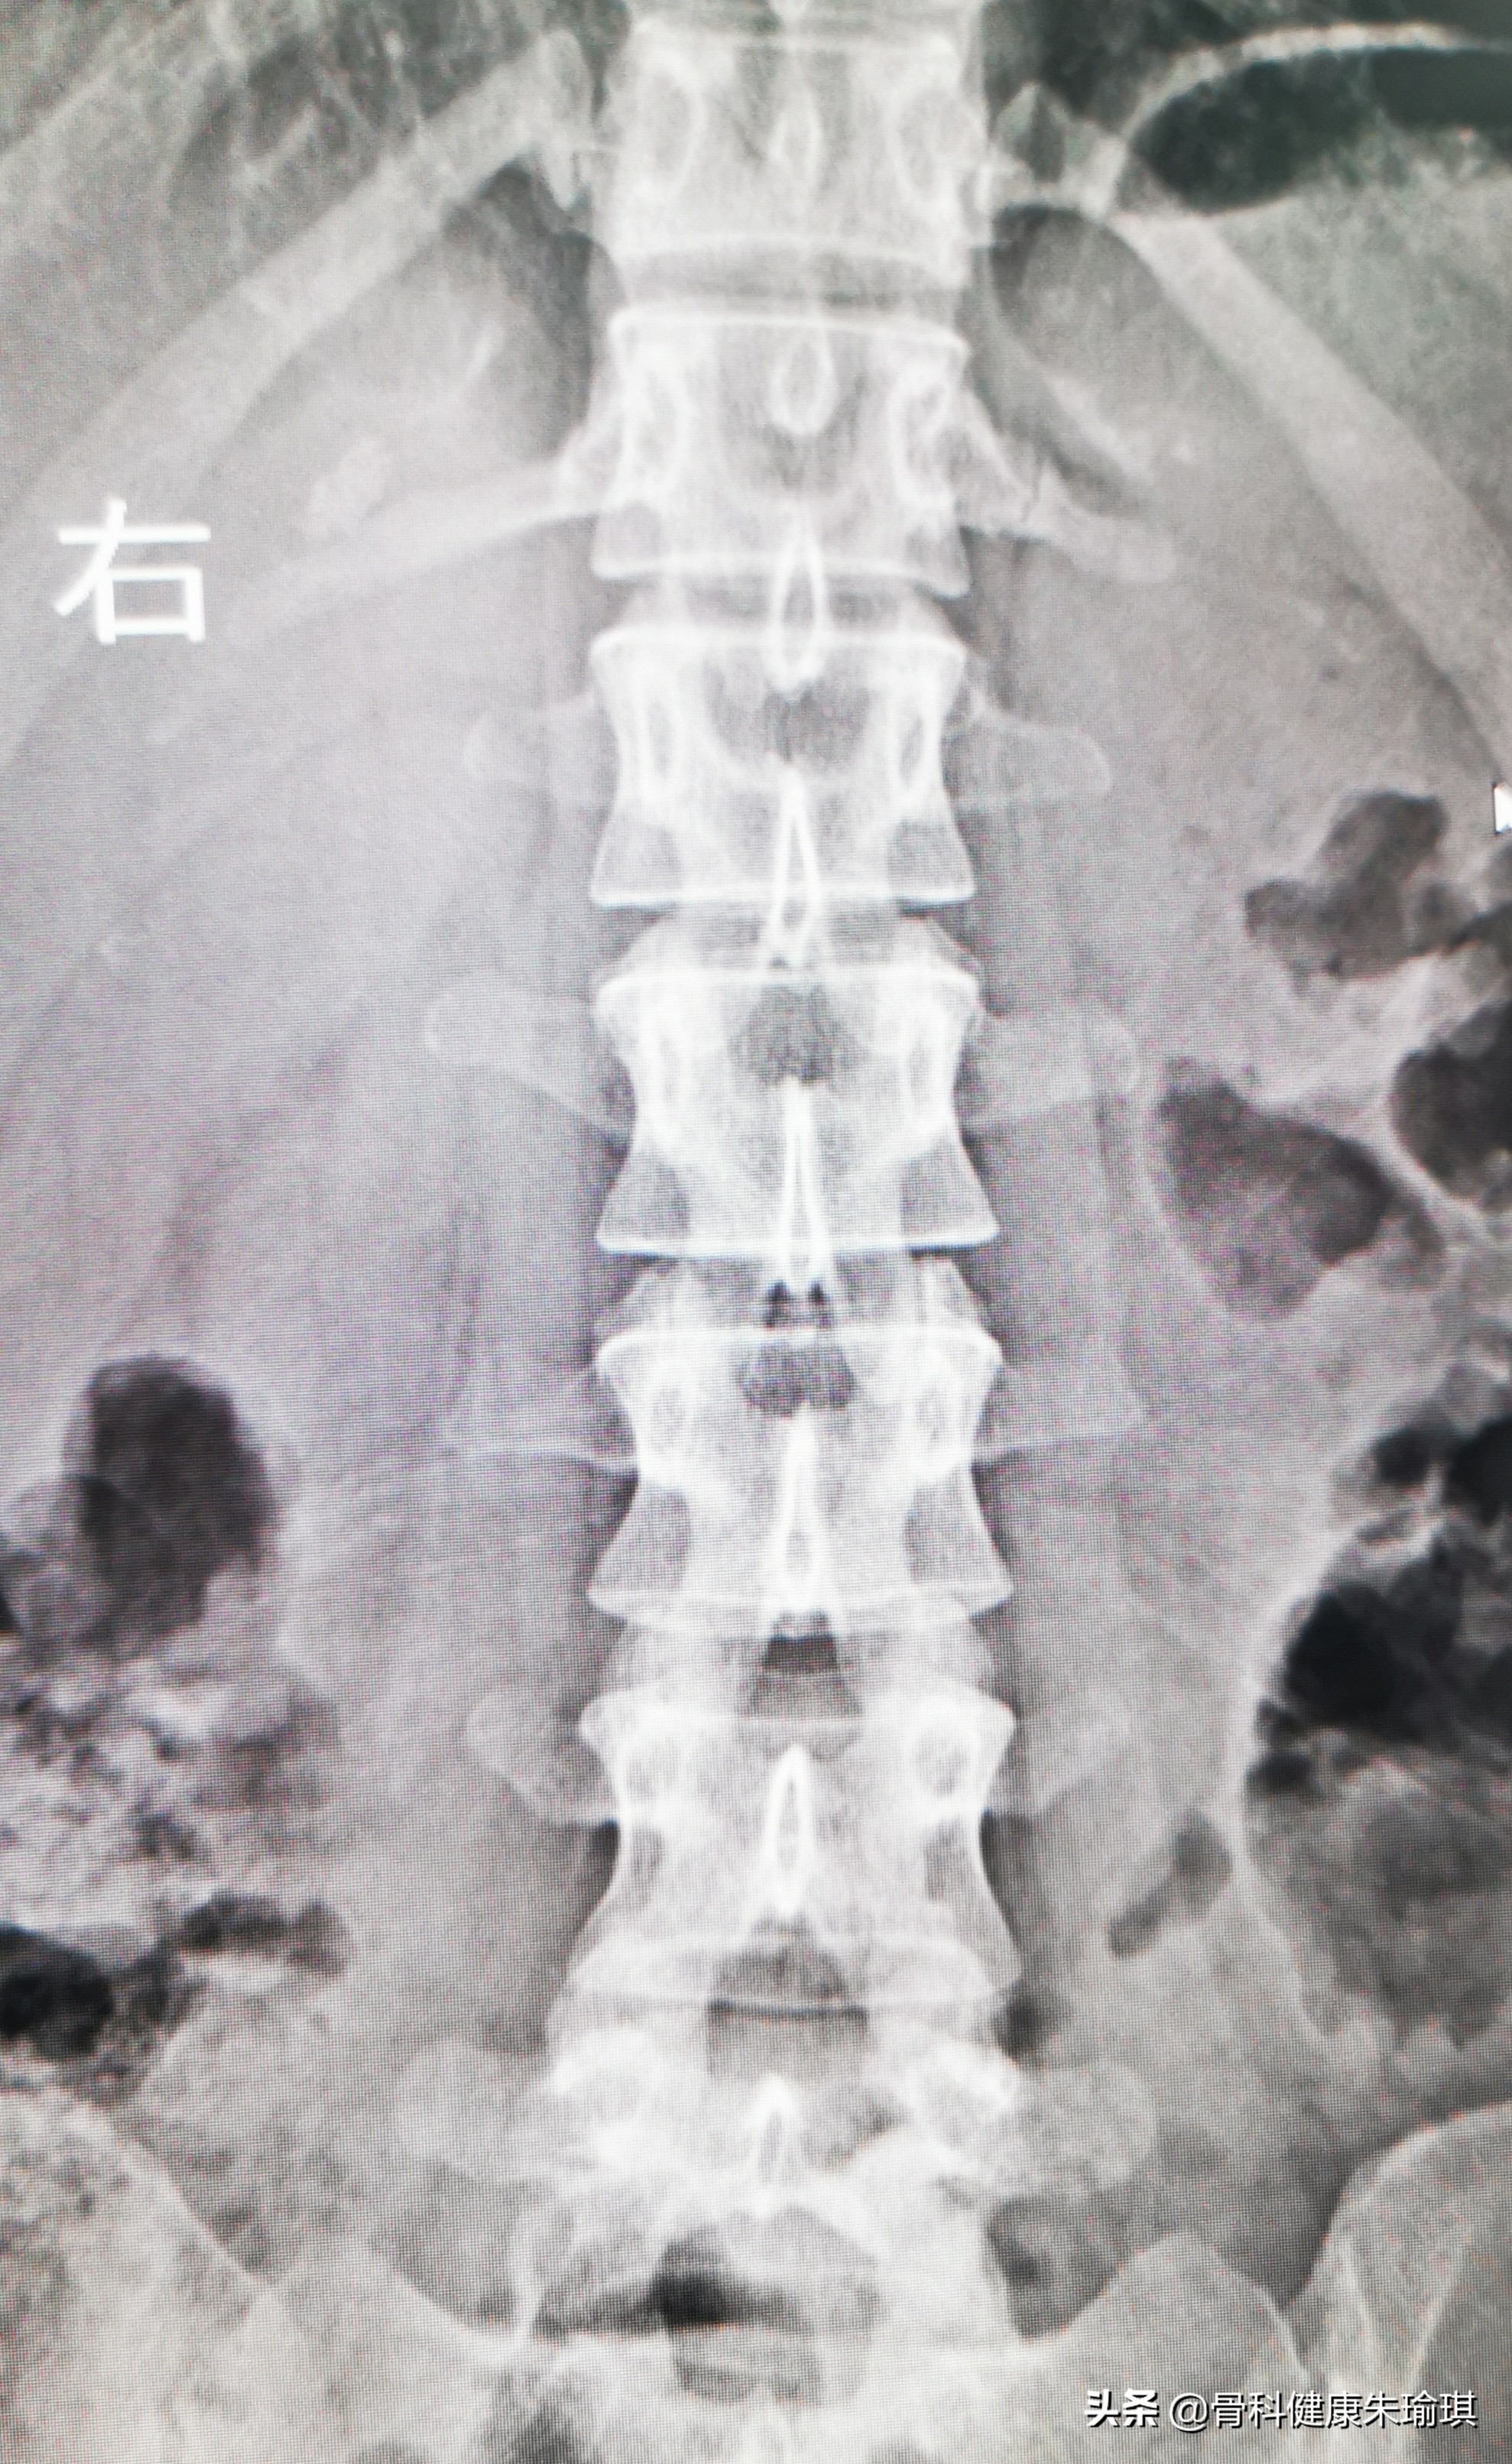

腰椎正位片

不怕!我告诉她。然后我仔细的询问了受伤的体位、力量的大小和扭伤后腰部疼痛的具体部位,然后我又看了带来的腰椎平片。

病人也把放射科的报告递给我,只见报告的诊断上清楚的写着:腰1左侧横突骨折!但仔细阅片,如果说怀疑是骨折,感觉这不是一个新鲜的骨折,因为看到的裂缝比较明显,两端都有部分的硬化。当时腰部扭伤的力量并不大,扭伤以后腰部虽有疼痛和活动不灵便,但并没有固定的剧烈疼痛点。

再仔细看片,不对啊,这不是腰椎啊,这分明是胸12椎体吗!右侧可以看到发育短小的第12肋骨(见下面图中箭头所指),由此可以推断,左侧的这个看似骨折的部位,并非腰椎横突,而是左侧的肋椎关节,只是这一侧的肋骨发育更加短小,小到跟腰椎的横突大小很一致罢了。

当我们明白了肋椎关节,特别是第11和12的肋头关节的特殊性以后,就更容易理解这个部位的结构,也可以确认这并非骨折。再看这张腰椎的片子,当我们具体定位了胸12椎体以后,再往下看(数),整个片子腰1、腰2、腰3、腰4、腰5都是序列非常完整排列的腰椎。